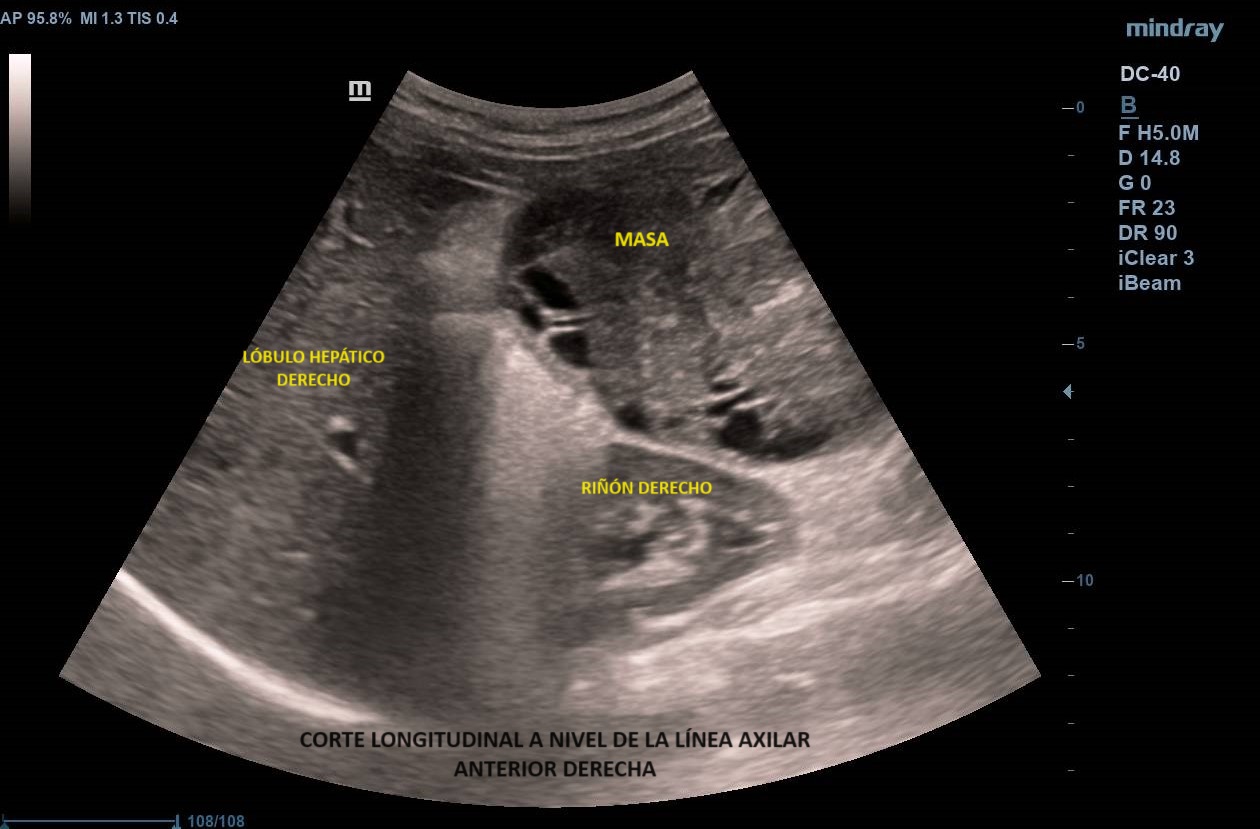

Ecografía abdominal clínica: Masa heterogénea que ocupa todo el abdomen, de aspecto sólido, vascularizada con zonas hipoecoicas-anecoicas en su interior. Riñones con eco-estructura sin alteraciones, hígado sin LOES. Vejiga sin engrosamiento de paredes, útero parcialmente visible. Anejos y retroperitoneo no valorables. No líquido libre.

Se deriva a urgencias donde realizan ecografía transvaginal confirmando presencia de masa que parece depender de anejo derecho. Solicitan TAC toraco-abdomino-pélvico objetivando «masa abdominal gigante de dudosa dependencia ovárica, no pudiendo descartar liposarcoma abdominal». Citan a la paciente para RM donde se demuestra contacto pero no dependencia de masa abdominal, probable liposarcoma, de anejo derecho, de características normales. Analítica con marcadores tumorales sin alteraciones.

Los leiomiomas uterinos son el tumor más frecuente de pelvis en la mujer. La ecografía es la primera línea de estudio. Habitualmente s

e describen como masas bien delimitadas redondeadas hipoecoicas con sombra acústica, aunque también pueden tener áreas isoecoicas e hiperecoicas. Pueden presentar necrosis central (áreas anecoicas) o calcificaciones, sin implicar malignización. El Doppler-color suele mostrar una distribución irregular de los vasos. El diagnóstico definitivo es el anatomo-patológico.